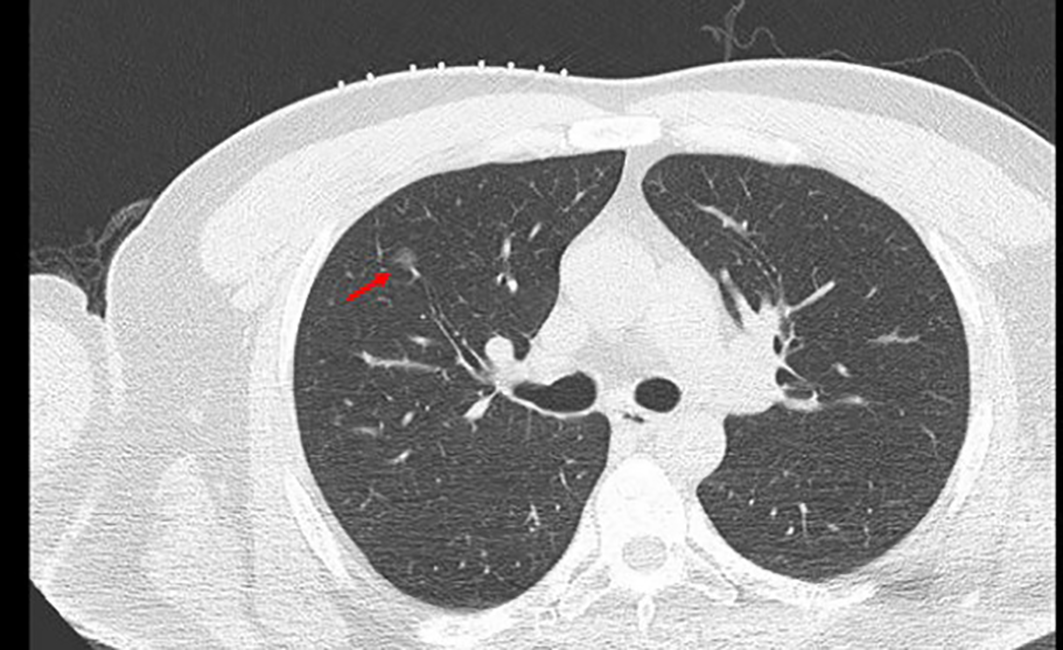

The patient underwent routine chest CT scanning before surgery (Figure 2). The relationships between the lesion and the blood vessels and bronchi were observed, and the appropriate scanning parameters and positions were determined. The surgeon performed CT-guided percutaneous puncture injection of medical glue for positioning and marking.

Figure 2

A ground glass nodule with small diameter, low density, and far away from the edge of the pleura. →, location of GGN; GGN, ground glass nodules.